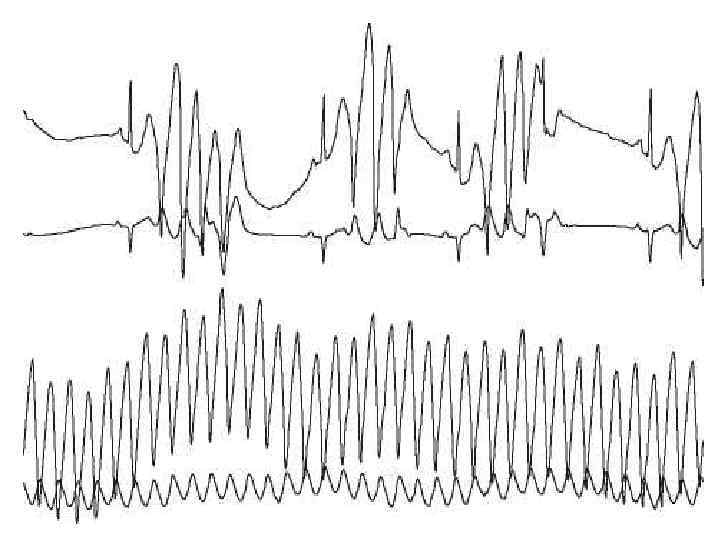

КЛИНИЧЕСКИЕ ПРОЯВЛЕНИЯ И ДИАГНОСТИКА (2). • Аритмический вариант стенокардии нередко проявляется синдромом МАС. Резкое снижение сердечного выброса при этом приводит к расстройствам гемодинамики (аритмогенный шок) и церебральным расстройствам вплоть до развития ОНМК и комы. При этом риск внезапной смерти резко возрастает и составляет 20 -25% в год. • Часто наблюдается дизадаптационная (холодовая) стенокардия и стенокардия de cubitas. • На клинические проявления стенокардии в пожилом возрасте существенное влияние оказывают хронические заболевания: СД, анемия, ГБ, ХНЗЛ, язвенная болезнь желудка, хронический панкреатит, хронический холецистит, ДЭ, абдоминальный ишемический синдром и др.

ОСОБЕННОСТИ ТЕЧЕНИЯ ИБС НА ФОНЕ ЗАБОЛЕВАНИЯ, СВОЙСТВЕННЫМ ПОЖИЛЫМ (6). • Те или иные НРС встречаются практически у всех пациентов с ИБС пожилого возраста. Наиболее часто встречается ФП, ТП, ЭА. Нередко – СССУ, АВ блокады. Помимо ИБС роль триггерных механизмов играют прогрессирование СН, электролитные нарушения, висцерокардиальные рефлексы, психогенные нарушения, аритмогенный эффекты СГ, БАБ, АК. • Атеросклеротическая энцефалопатия существенно влияет на клинику и течение ИБС. Если после ИМ к активному образу жизни возвращается более 40% пациентов пожилого и старческого возраста, то при наличии АДЭ – не более 20 -25%.